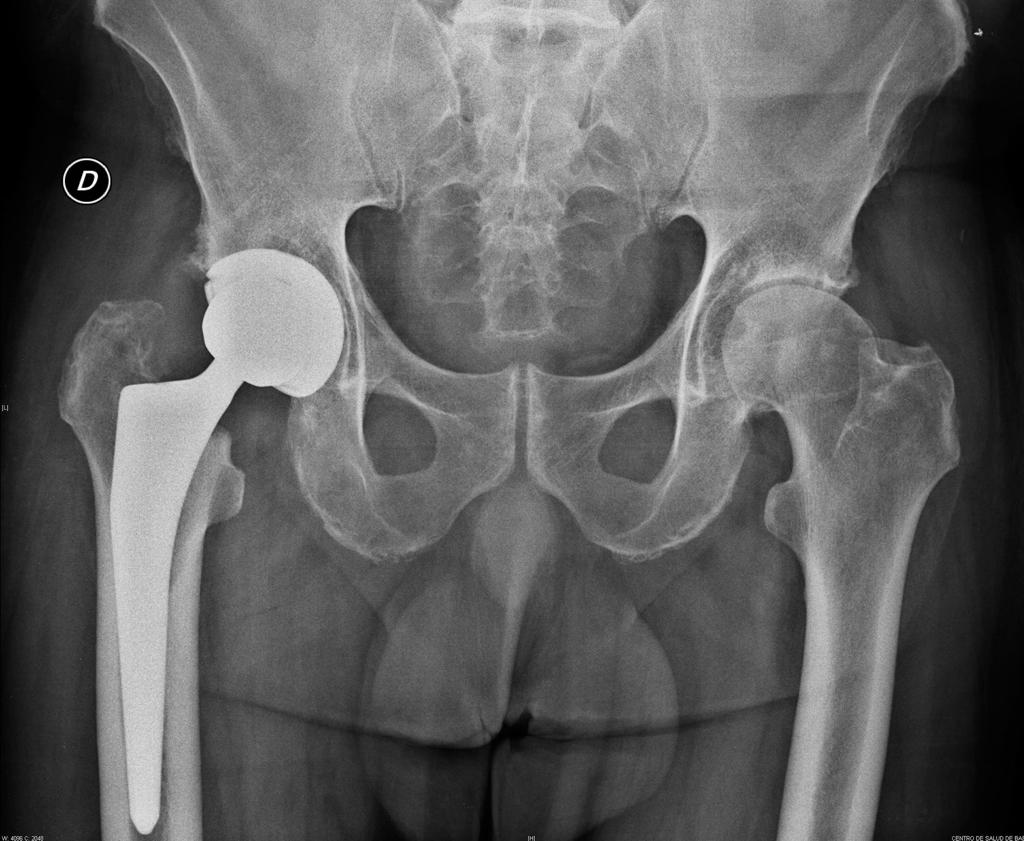

A continuación os mostramos el antes y el después de un caso clínico tratado por nuestro equipo de traumátologos.

- Cada paciente es completamente diferente pero, de forma general, podemos afirmar que uno de los principales beneficios que nota el paciente tras una cirugía de reemplazo de cadera es la disminución o desaparición del dolor inguinal que suele presentar previamente. Y suele ir acompañada de una importante mejora en la movilidad de la articulación.

- Otro de los beneficios asociados, suele ser la corrección de la dismetría que presentan algunos pacientes con artrosis de cadera.